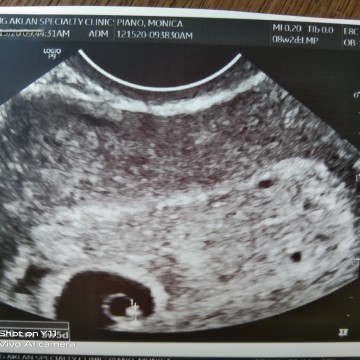

Buntis ako ng 2months and 2days ngayon

Hello po god afternoon buntis ako 2months and 2days ngayon ng tatanung po ako meron pong buntis na dinudugo parin kahit buntis na siya pakisagot naman po kong meron